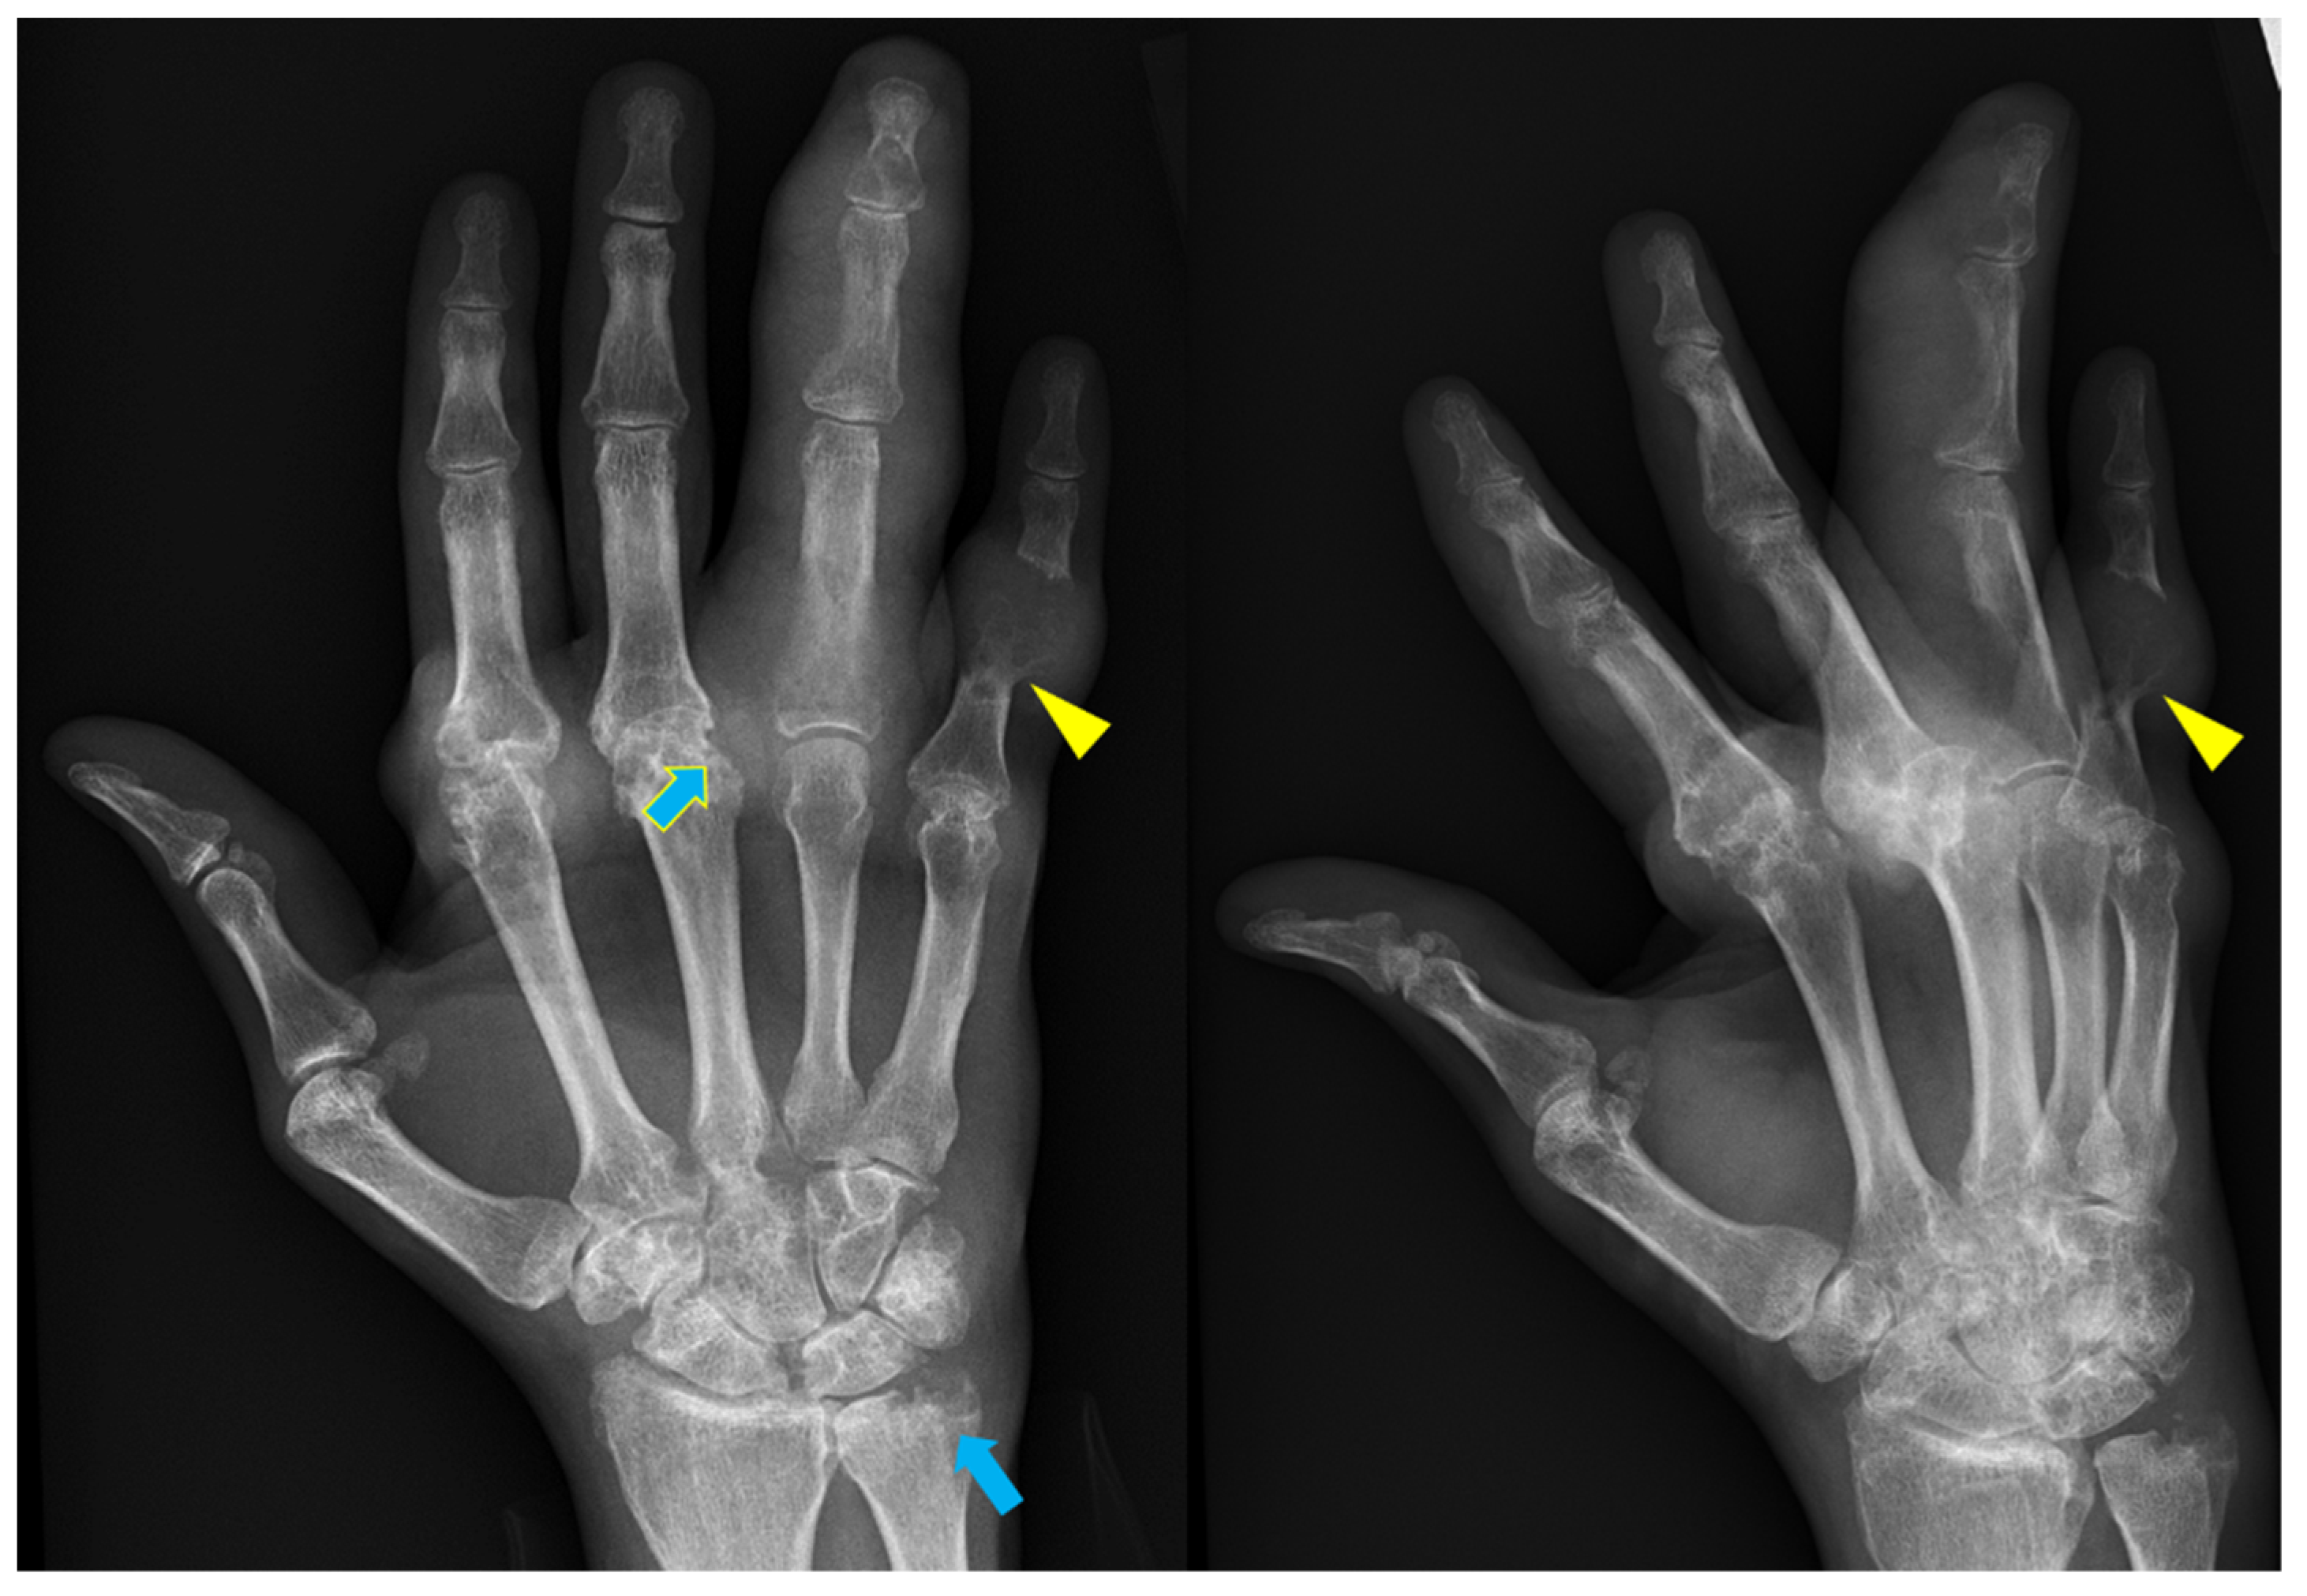

— Apakah Anda benar-benar berpikir bahwa pijat atau analgesik dapat mencegah kerusakan sendi dan tulang rawan? Itu adalah kesalahpahaman besar. Obat-obatan dari apotek tidak dapat meregenerasi jaringan, sementara bahan kimia yang terkandung di dalamnya justru merusak hati dan ginjal seiring waktu. Tubuh tidak dapat selamanya menanggung beban racun ini, dan alih-alih menyelesaikan masalah, Anda justru meracuni diri sendiri! Hal ini terutama berlaku untuk tulang belakang. Semua sendi mengalami keausan, tetapi pada tulang belakang, kurangnya ujung saraf dapat menyembunyikan perubahan yang berbahaya. Kompresi saraf skiatik akibat hernia adalah proses yang menyakitkan, awalnya menyebabkan nyeri ringan di punggung bawah, lalu menjalar ke kaki, menyebabkan kesemutan, mati rasa, dan akhirnya hilangnya fungsi kaki sepenuhnya. Kerusakan yang terus berkembang akan menyebabkan kelumpuhan pada bagian bawah tubuh, dan mengembalikan kendali atasnya menjadi hampir tidak mungkin. Lihat gambar ini. Ini adalah kondisi tulang belakang seseorang yang baru berusia 44 tahun, tetapi tampak seperti lansia. Dulu, kerusakan seperti ini hanya terjadi setelah usia 60 tahun, tetapi sekarang hal ini menjadi umum bagi mereka yang baru saja melewati usia 40 tahun. Kerusakan ini akan terus berkembang seiring bertambahnya usia, dan mengabaikannya berarti menempatkan diri dalam risiko kelumpuhan total!

Tulang belakang pasien berusia 44 tahun: semuanya dimulai dengan nyeri ringan, tetapi hanya dalam satu minggu muncul hernia, dan dalam dua minggu terjadi pergeseran tulang belakang, tekanan pada saraf, dan akhirnya—kursi roda.

Jari tangan bengkok akibat keausan akibat usia dan artritis lanjut.